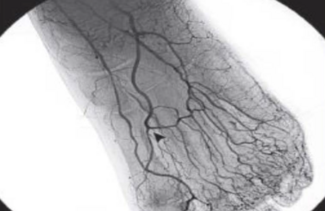

The authors review pedal artery revascularization, which has been associated with improved wound healing and limb salvage.